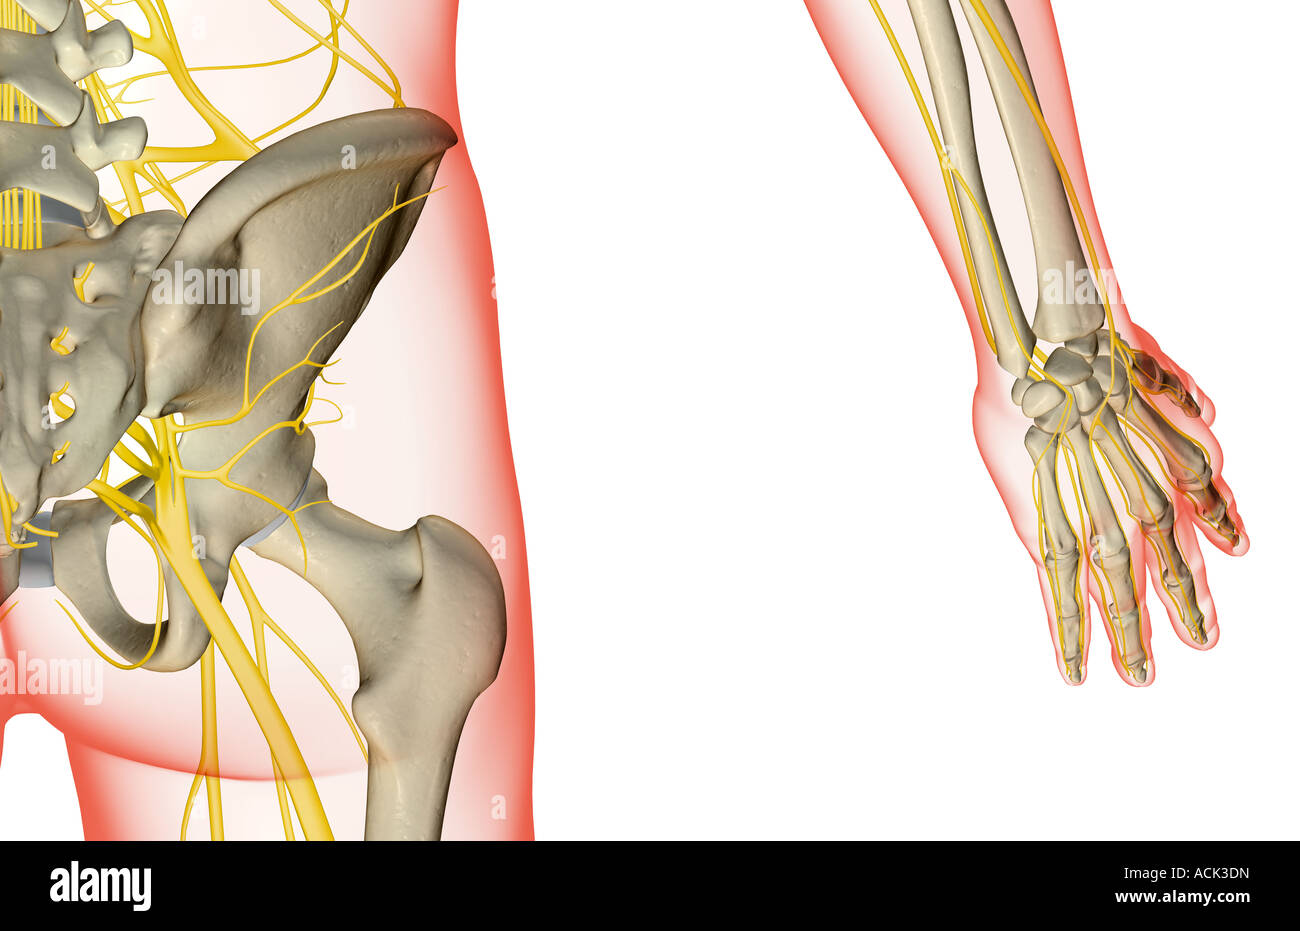

Les nerfs de la hanche Banque D'Imageshttps://www.alamyimages.fr/image-license-details/?v=1https://www.alamyimages.fr/photo-image-les-nerfs-de-la-hanche-13175504.html

Les nerfs de la hanche Banque D'Imageshttps://www.alamyimages.fr/image-license-details/?v=1https://www.alamyimages.fr/photo-image-les-nerfs-de-la-hanche-13175504.htmlRFACK3DN–Les nerfs de la hanche